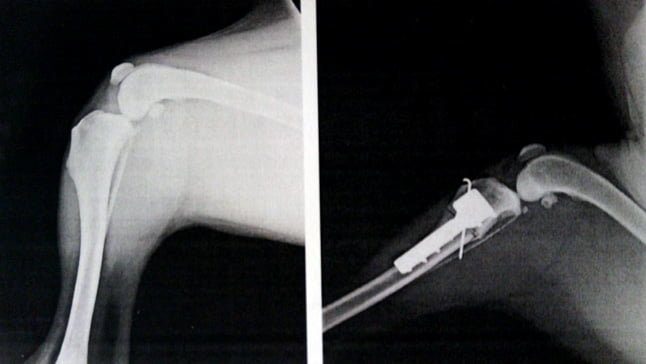

El diagnóstico confirmativo se realiza a través de imagen (radiografía), además de tests diagnósticos de rutina que el especialista le practicará.

Operación quirúrgica TTA

Aunque no es una operación a corazón abierto, no deja de ser una operación importante. Consiste en el avance de la tuberosidad tibial, es decir eliminar un pequeño trozo de hueso y usar una placa para que la soldadura se realice correctamente.

Con esto se consigue destensar el ligamento, evitando así que sufra y en consecuencia reduciendo la inflamación y dolor en el perro. Esta técnica ofrece unas tasas de éxito bastante elevadas.